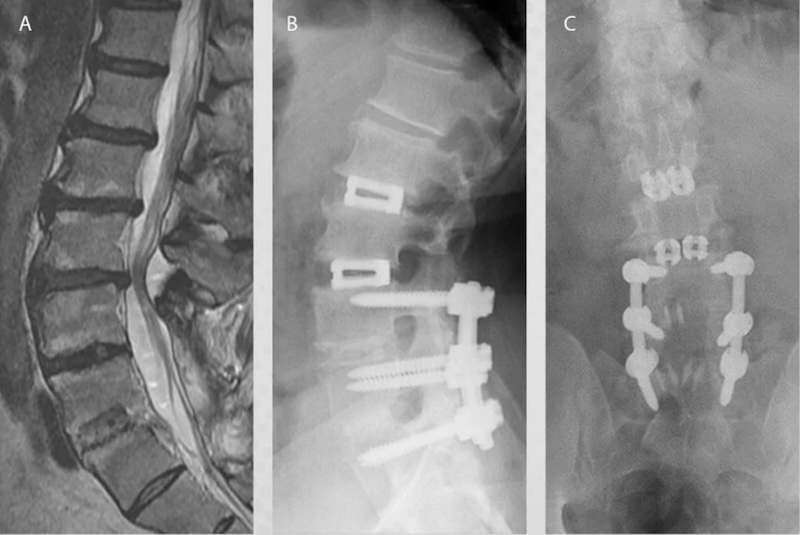

The VariLift-LX by Wenzel Spine is a threaded no-impact TLIF or PLIF Interbody spacer that is indicated for stand-alone or with supplemental fixation. The VariLift-LX features an expandable anterior expansion up to 9 degrees through insertion of self-locking expansion plate. The Cage is threaded in either unilaterally (TLIF) or bilaterally (PLIF) and expanded by pushing the expansion plate forward.The cage can be back filled with graft material.